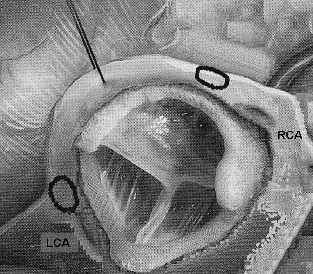

The Contribution of Echocardiography in the Dysfunctions of Mechanical Prosthesis: Report of 11 Cases

Saloua Oummou*, Abir Abardazzou, Salwa Karimi, Dounia Benzeroual, Mustapha Elhattaoui